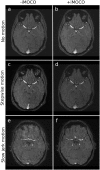

Introduction: Subject movements lead to severe artifacts in magnetic resonance (MR) brain imaging. In this study we evaluate the diagnostic image quality in T1-weighted, T2-weighted, and time-of-flight angiographic MR sequences when using a flexible, navigator-based prospective motion correction system (iMOCO).

Methods: Five healthy volunteers were scanned during different movement scenarios with and without (+/-) iMOCO activated. An experienced neuroradiologist graded images for image quality criteria (grey-white-matter discrimination, basal ganglia, and small structure and vessel delineation), and general image quality on a four-grade scale.

Results: In scans with deliberate motion, there was a significant improvement in the image quality with iMOCO compared to the scans without iMOCO in both general image impression (T1 p<0.01, T2 p<0.01, TOF p = 0.03) and in anatomical grading (T1 p<0.01, T2 p<0.01, TOF p = 0.01). Subjective image quality was considered non-diagnostic in 91% of the scans with motion -iMOCO, but only in 4% of the scans with motion +iMOCO. iMOCO performed best in the T1-weighted sequence and least well in the angiography sequence. iMOCO was not shown to have any negative effect on diagnostic image quality, as no significant difference in diagnostic quality was seen between scans -iMOCO and +iMOCO with no deliberate movement.

Conclusion: The evaluation showed that iMOCO enables substantial improvements in image quality in scans affected by subject movement, recovering important diagnostic information in an otherwise unusable scan.